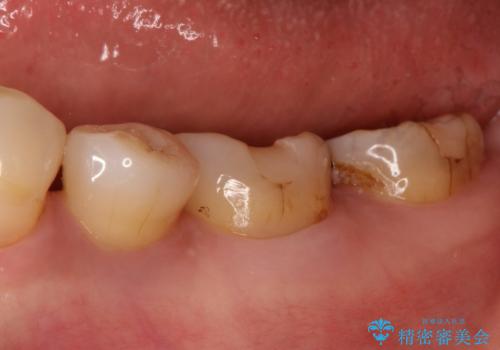

- 以前治療したところがしみて、アイスが食べられないから被せものの治療をしてほしいと来院された患者様です。

咬合が強く、歯牙にマイクロクラックが入っている状態でした。歯髄は保存可能と診断され、フルジルコニアクラウンによる治療を行いました。

咬合面に広範囲の修復物がある状態で中心に強い力が加わると歯牙は外方性の歪みが生じ、マイクロクラックができます。これを防ぐには、咬頭被覆するアンレー、もしくはクラウンによる治療が必要です。